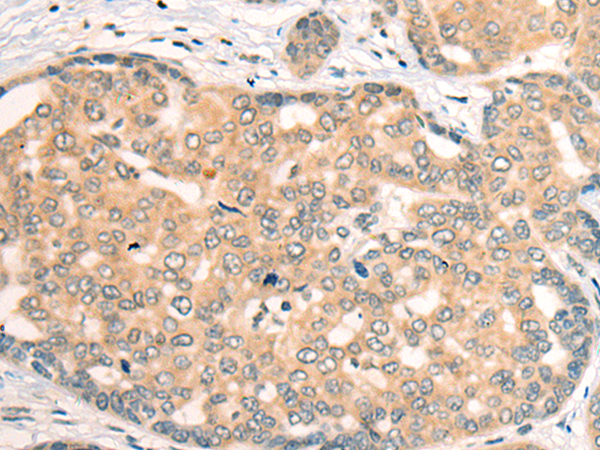

分类: 科研抗体货号: P09491别名: CFP1; CGBP; SPP1; PCCX1; PHF18; hCGBP; ZCGPC1; HsT2645; 2410002I16Rik; 5830420C16Rik应用: IHC反应种属: Human, Mouse